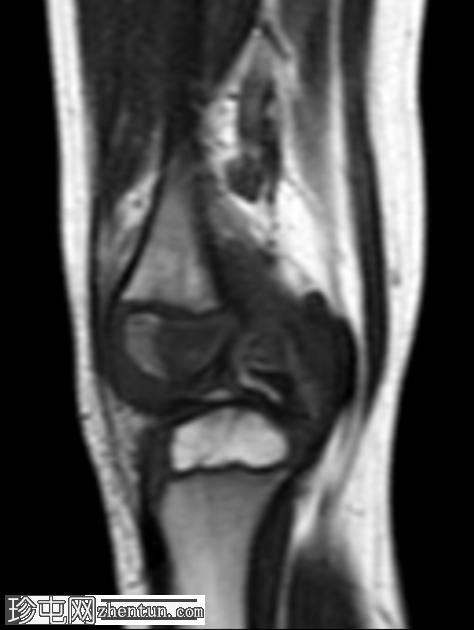

3.png

矢状位

T1加权像

右膝专用MRI显示股骨外侧髁后方髓内有一边界清晰的病灶,大小为1.6 x 0.9 cm,中心T1呈低信号,T2/STIR呈高信号,周围可见薄层T1高信号环(半影征)。

其MRI主要特征是“半影征”——围绕中央脓肿腔的T1加权中高信号强度肉芽组织环,脓肿腔内充满T1低信号的脓液。